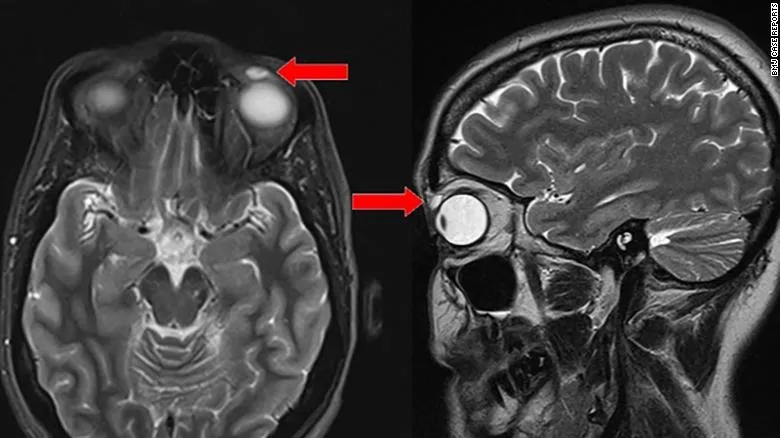

Phần kính áp tròng mắc kẹt trong mí mắt. Ảnh: BMJ Case Reports.

Các chuyên gia về mắt ban đầu cho rằng đó chỉ là một u nang chứa dịch với kích thước 8 x 4 x 6 mm nên sau đó đã quyết định lấy bỏ nó ra khỏi mắt bệnh nhân. Nhưng sau khi ca tiểu phẫu hoàn thành, họ mới phát hiện cục u đó thực chất là chiếc kính áp tròng dính vào mí mắt bệnh nhân cách đây 28 năm.

Khi lấy dị vật ra, các bác sĩ phẫu thuật vô cùng kinh ngạc khi phát hiện ra khối u này thực sự là một chiếc kính áp tròng đã rạn vỡ. Ảnh: CNN